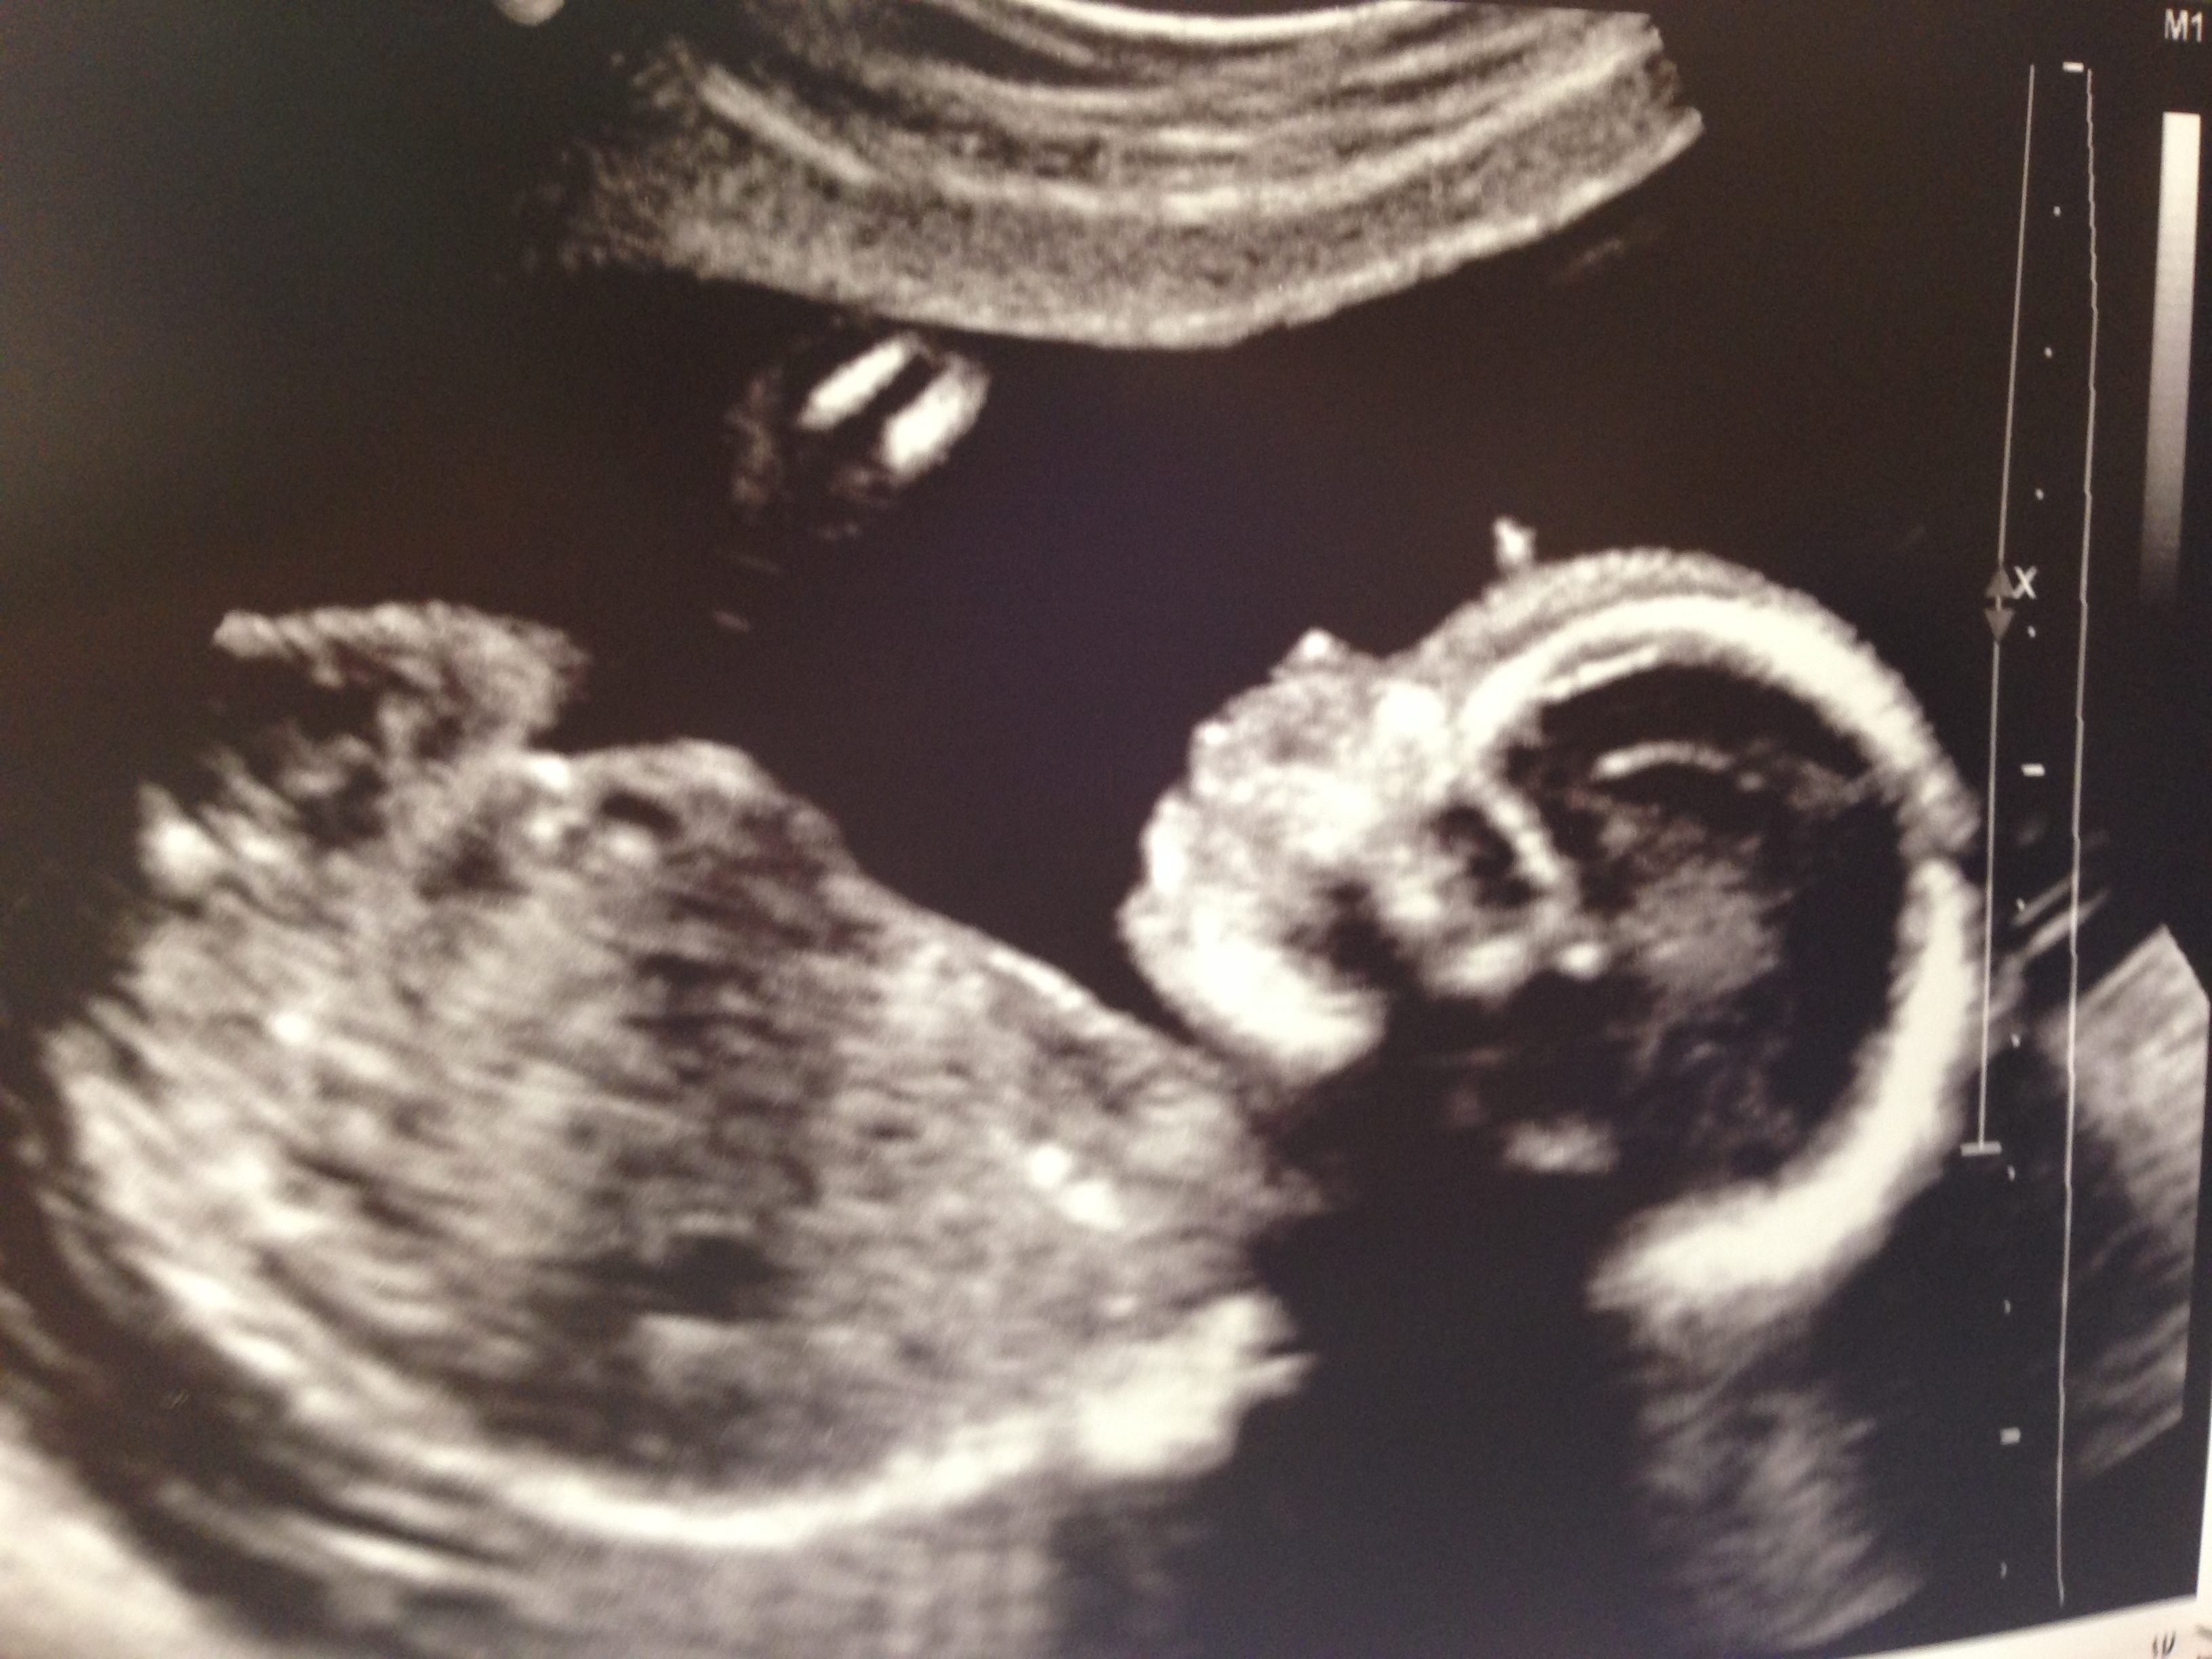

Isn’t he handsome? Look at that nose. He had my nose. And those toes? Stop it.